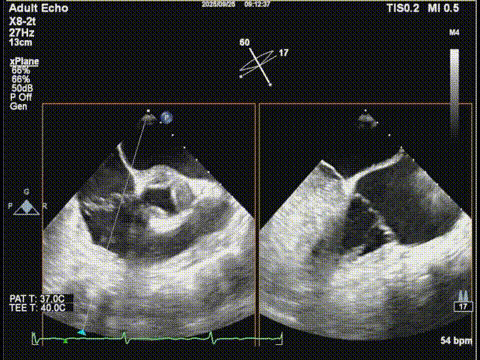

术前食道超声:

房颤,瓣环扩大的房性二尖瓣反流,反流主要集中在二区,二区后叶部分脱垂,后叶的长度16mm,前叶的长度是37mm。房间隔整体的条件可,从瓣环到拟定的卵圆窝顶部高度大概是41mm。

二尖瓣2区

二尖瓣2区color